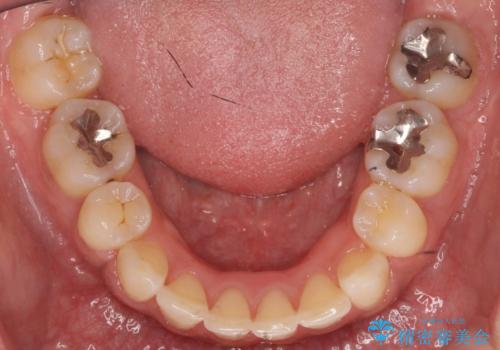

- 治療計画

- 前歯を下げたいと来院。

初めは、上だけ抜歯しましたが、もう少し口元を下げたいとのことで追加で下顎を抜歯しました。

年齢の割に歯が動きにくかったこともあり、また、追加で抜歯して結果として時間がかかってしまいました。口元が大きく下がり、結果には満足していただけました。

横顔が大きく変わり、満足していただけました。